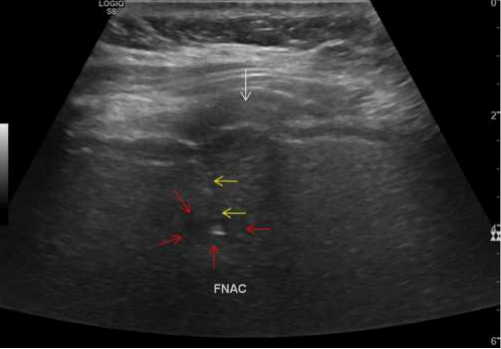

Figure 05: 42Y/Female, known case of carcinoma breast with new onset 5 mm lesion in segment VIII of liver. Note the location of the lesion beneath the rib. Needle was inserted in this small lesion in breathhold during inspiration. White arrow denotes rib, red arrows denote the liver lesion and yellow arrow denotes the spinal needle with its tip inside the liver lesion. Background liver shows fatty infiltration. Cytology report suggestive of reactive atypia in the liver lesion.